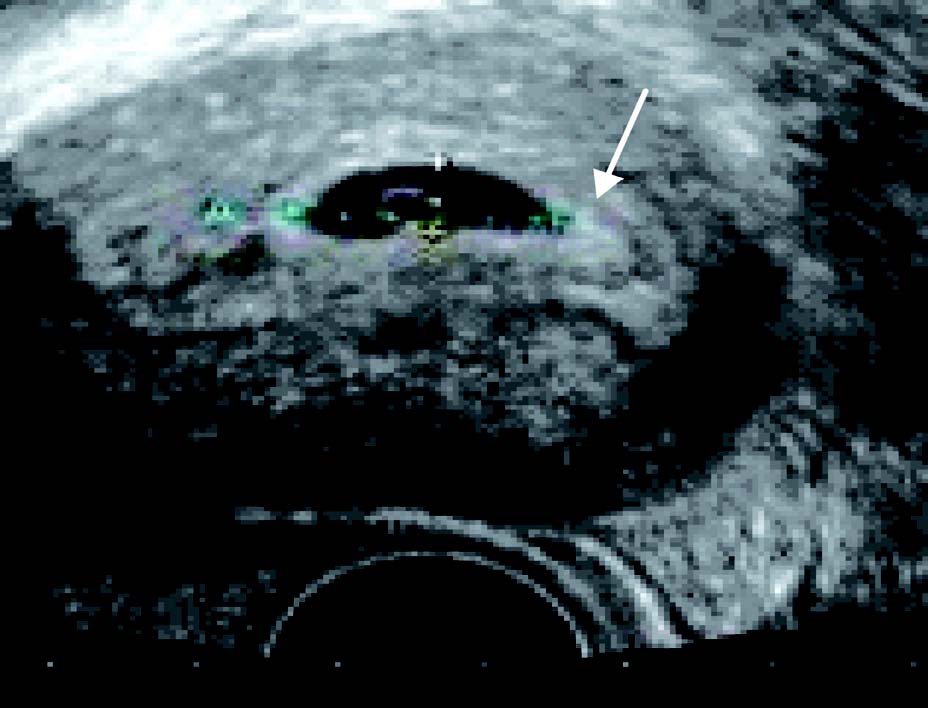

1.妊娠4~5周超声表现:①子宫增大,子宫内膜增厚,内膜内宫腔线的一侧见圆形增强回声区,中央有小囊状液性暗区,为极早期的妊娠囊;②妊娠囊内可见卵黄囊的环形结构,正常直径2.0~5.6 mm;③双蜕膜征或双环征:宫腔少量出血后壁蜕膜和包蜕膜构成的特征性双环结构。检出“双环征”或妊娠囊内见到卵黄囊或胚胎可确定早孕。

患者25 岁。停经35 天,尿HCG(+)。经阴道超声后位子宫纵切面:宫腔内见偏于一侧内膜的圆形囊性结构为胚囊(GS),称偏心圆;囊壁规则,呈中高回声,内部无回声;胚囊前后径2.7 mm;经阴道超声后位子宫横切面:测得胚囊横径为3.0 mm

超声诊断:宫内早早孕。